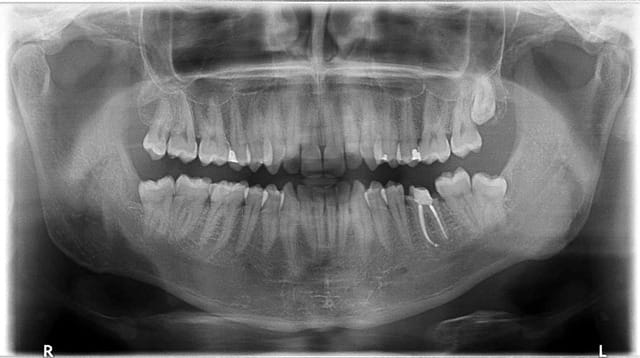

Je viens de voir vendredi dernier un patient (cousin d'une connaissance) à qui l'on vient de faire sur Paris (en 2013!) plusieurs traitement endo + ccm, et il présente aujourd'hui sur quasi chacune des dents couronnées une lésion apicale plus ou moins étendue, avec douleurs exacerbées à la pression (et à la percussion verticale)...